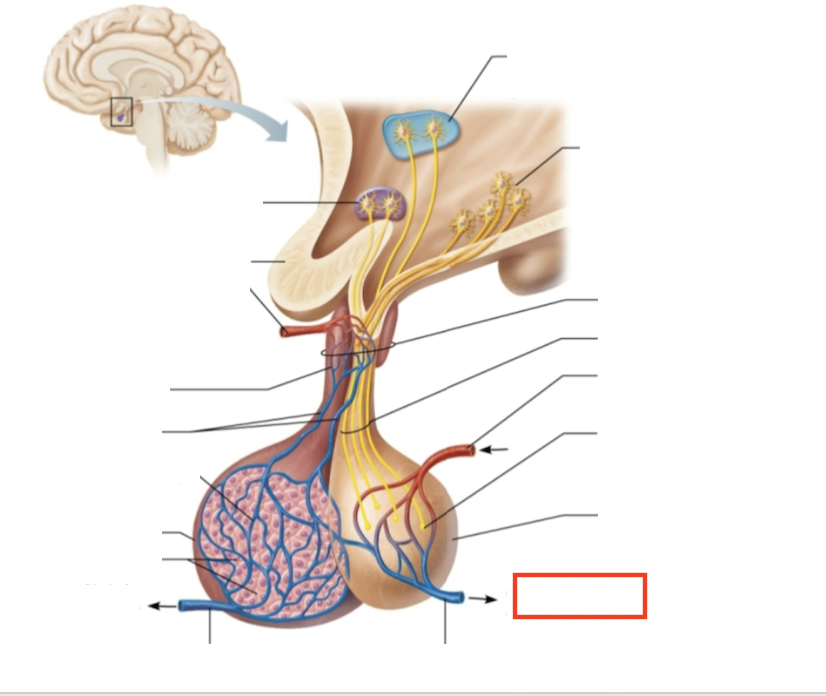

What structure is highlighted?

testes (male)

What are the target organs and effects of testosterone?

most cells of the body; promotes the maturation of the male reproductive organs, the development of secondary sex characteristics, sperm production, and sex drive

What hormone is produced by the testes?

testosterone

What stimulates testosterone production?

LH and FSH